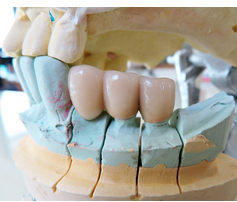

- 임플란트 복원: 임플란트가 안정적으로 고정되면 인공 이빨이 부착됩니다. 이 단계에서는 임플란트를 지지할 구조물인 프레임이나 초록색 인상물 등을 설치하고, 세라믹, 금속, 합금 등으로 만들어진 인공 이빨을 부착합니다.

- 인공 이빨 삽입: 오스테오인테그레이션이 완료된 후, 치과 의사는 인공 이빨을 임플란트에 부착하여 보철 수술을 마무리합니다.